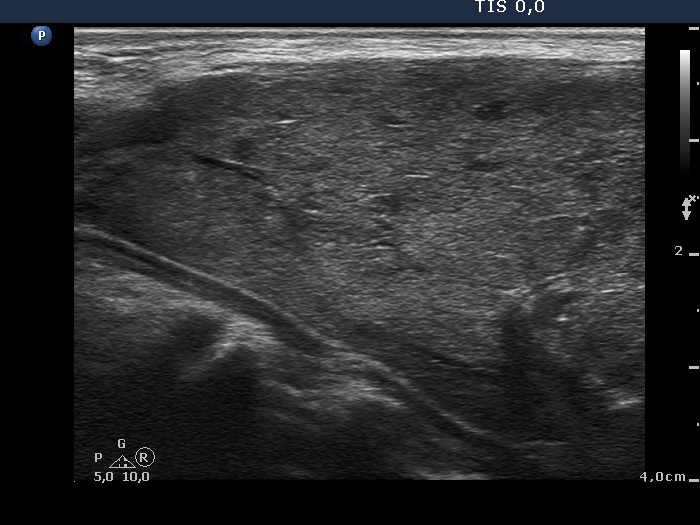

The operated thyroid - case 710 (ultrasonographic picture 2)

Right lobe, longitudinal scan. Note the presence of fibrosis.